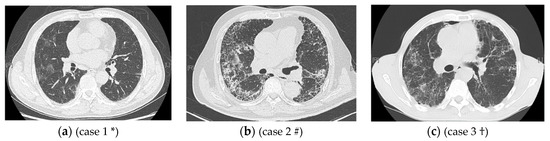

In the second part of the artificial intelligence method of this study, after identifying the imaging features with the CNN model and calculating the area percentages of each imaging feature, the latter were used as the input and glucocorticoid sensitivity as the output to develop correlation models with the KNN and SVM algorithms. Since only 45 patients were treated with glucocorticoids, the training set was used as the validation set, and the KNN and SVM algorithms were applied to assess the correlation of the imaging findings with glucocorticoid sensitivity, achieving accuracies of 0.82 and 0.80, respectively. The KNN algorithm slightly outperformed the SVM algorithm, suggesting that the KNN model had greater resolution in identifying glucocorticoid sensitivity. Thirty-four patients were included in the glucocorticoid-sensitive group, and eleven patients were included in the glucocorticoid-insensitive group. The accuracy of the model in identifying glucocorticoid sensitivity was 1, while the positive predictive value of the model in identifying glucocorticoid insensitivity was only 0.27. The reasons for the low positive rate of the model in identifying patients with glucocorticoid insensitivity are as follows: The algorithm design does not attempt to identify glucocorticoid sensitivity by factors other than the area percentages of the imaging features. In addition to previous research results indicating that the combination of reticulations and honeycombing areas on HRCT is related to glucocorticoid sensitivity, different HRCT imaging features may be present, and their different relative area percentages could result in different glucocorticoid effects. By reviewing the HRCT images of all patients treated with glucocorticoids in this study, we observed that IIP patients typically presented with one of the following patterns: mainly ground glass opacities with almost no reticulations or honeycombing; mainly reticulations or honeycombing but almost no ground glass opacities; and ground glass opacities, reticulations, honeycombing, and consolidations coexisting in the same or similar proportions. When the imaging features were primarily ground glass and there were few reticulations and little honeycombing, the patient was more likely to be sensitive to glucocorticoids, and the accuracy of the AI model was high. When the imaging features were ground glass opacities, reticulations, and honeycombing, the model had to consider the ratio of the area of ground glass opacities to that of the combination of reticulations and honeycombing; a greater area ratio was more predictive of glucocorticoid sensitivity. If the imaging features included ground glass opacities, reticulations, honeycombing, and consolidations, the greater the ratio of the area of ground glass opacities plus consolidations to the area of reticulations plus honeycombing, the more sensitive the patient was likely to be to glucocorticoids. Figure 4a shows the chest CT of a 63-year-old male, which primarily presents with ground glass opacity (accounting for 21.6% of the area), while reticulations account for 0.06%. The AI model labeled this patient as sensitive to glucocorticoids, matching the actual glucocorticoid effect. A 67-year-old male, whose CT images are shown in Figure 4b, was correctly identified as insensitive to glucocorticoids through the AI model. Reticulations accounted for 49.8% of the area, honeycombing accounted for 15.3%, and the sum of the two accounted for 65.1%. The CT images of a 64-year-old male shown in Figure 4c can be mainly characterized by ground glass opacities (15.1% of the area), reticulations (37.54%), and honeycombing. The AI model classified this patient as glucocorticoid sensitive, but he was actually insensitive to glucocorticoids. Overall, among the samples of this study, the accuracy in identifying the glucocorticoid-sensitive group was acceptable, while that in identifying glucocorticoid-insensitive individuals needs to be improved. By expanding the number of patients, other factors that may affect the efficacy of glucocorticoids can be added to construct the AI model.

Figure 4.

Different imaging manifestations of HRCT may affect the judgment of AI on glucocorticoid sensitivity. * Case 1 HRCT mainly shows ground glass opacity and was correctly identified as sensitive to glucocorticoids using the AI model. # Case 2 HRCT shows mainly reticulations and honeycombing and was correctly identified as insensitive to glucocorticoids using the AI model. † Case 3 is mainly characterized by ground glass opacities, reticulations, and honeycombing and was incorrectly identified as sensitive to glucocorticoids using the AI model.